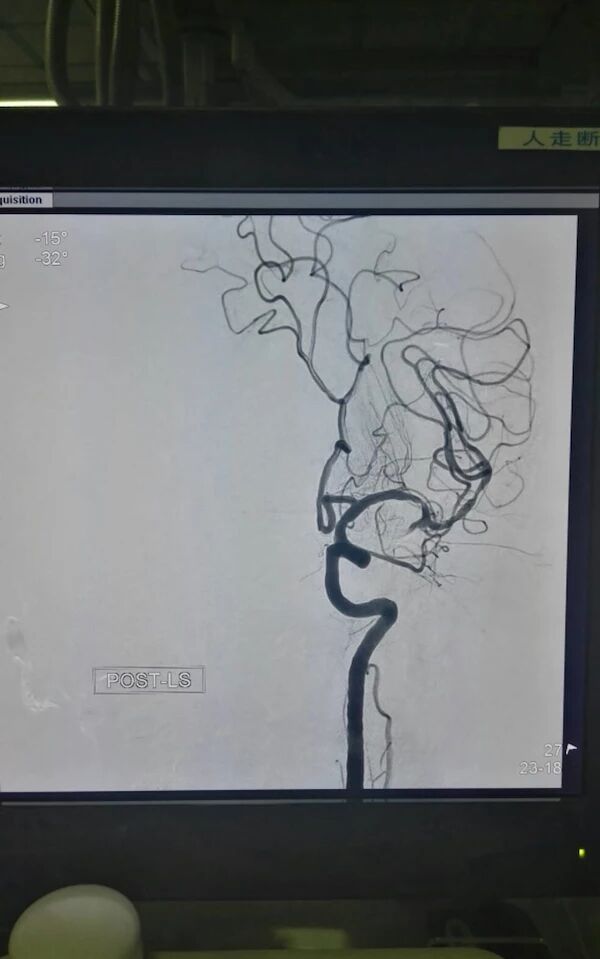

完善相关检查后,急诊行全脑血管造影术

示右侧大脑后动脉P1段不显影,右侧后交通动脉开放。左侧P1中段闭塞,左侧前循环无明显代偿。考虑该血管为责任血管,急诊行血管开通术。

行血管造影示:双侧大脑后动脉显影,远端血管快速充盈,TICI:3级,术毕。患者言语较前流利,可准确应答,左侧肌力恢复正常,NHISS评分1分。